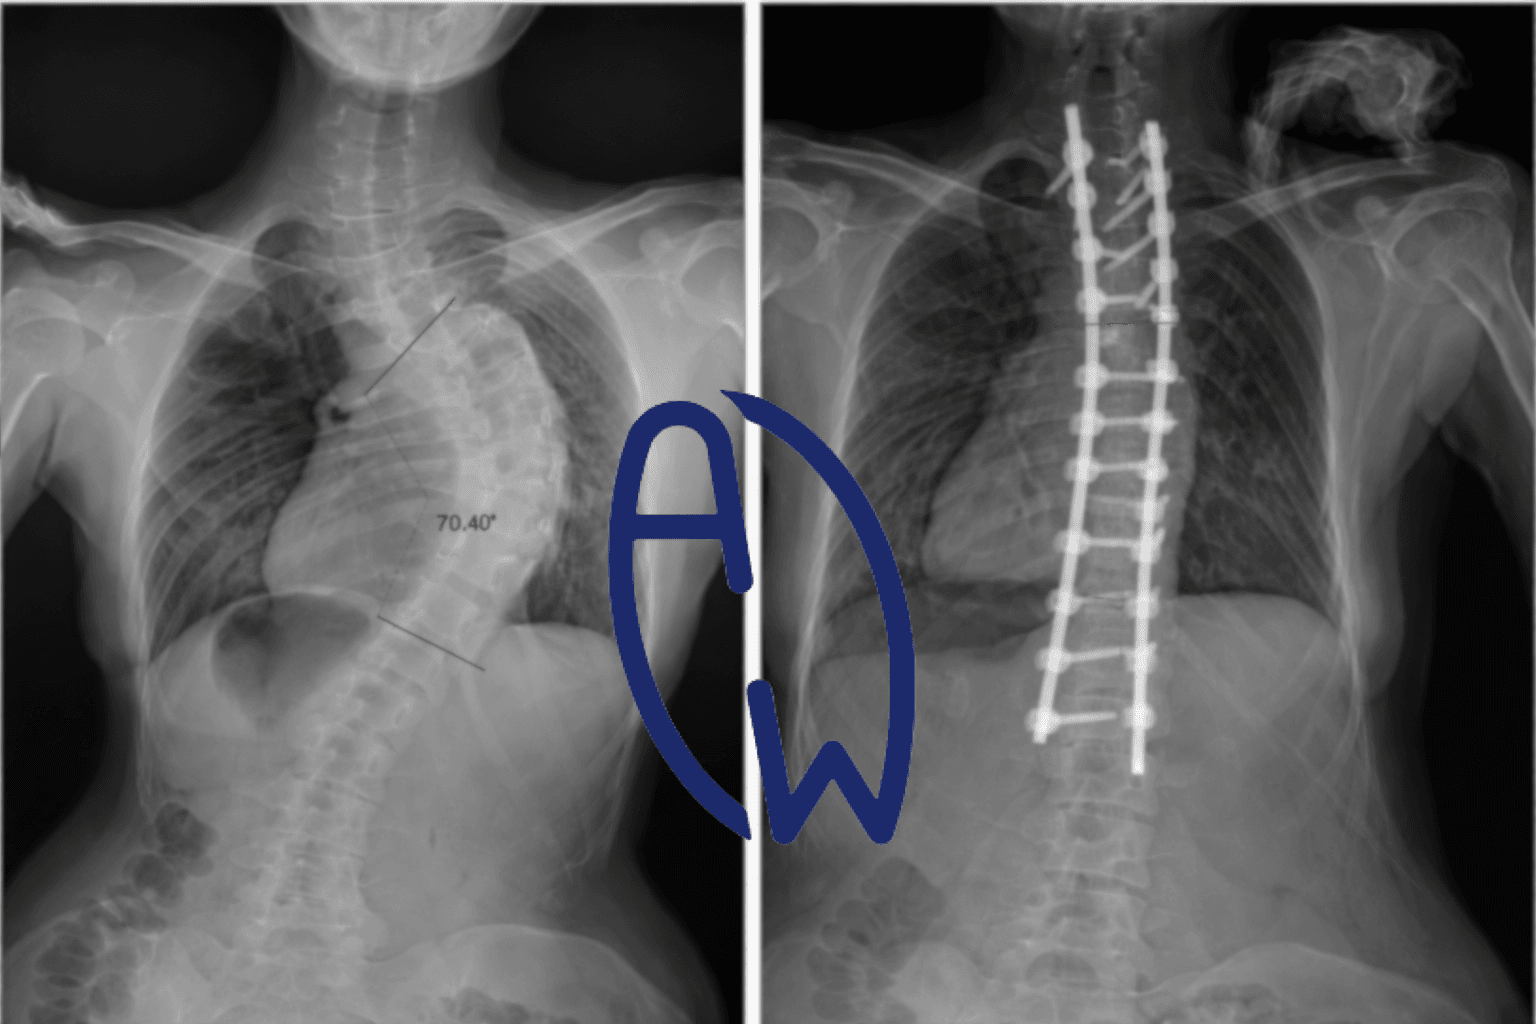

Pre-Operative State: Severe Thoracic Curve (~70–80°)

In severe thoracic scoliosis exceeding 70°, radiographs typically demonstrate:

Post-Operative Radiographic Correction

Post-operatively, Cobb angle reduction is often substantial.

Radiographic correction does not guarantee restoration of physiological lung capacity.

The image is shared for educational purposes with patient consent. Individual outcomes vary. Structural correction does not automatically restore full respiratory function. Clinical assessment is required.